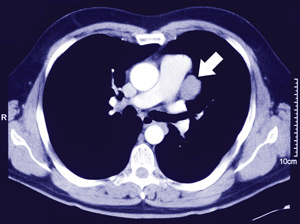

A 41-year-old man was referred for open biopsy of a 3 cm left lung lesion. The lesion had been discovered incidentally on chest x-ray (Box, A) and investigated with a computed tomography scan of the chest (Box, B) and a fine needle aspiration biopsy under radiological guidance that was inconclusive.

B: Computed tomography scan showing a well encapsulated mass (arrow) adjacent to the mediastinum.